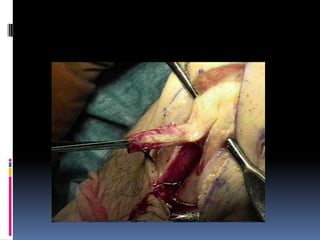

GRAFT HARVEST